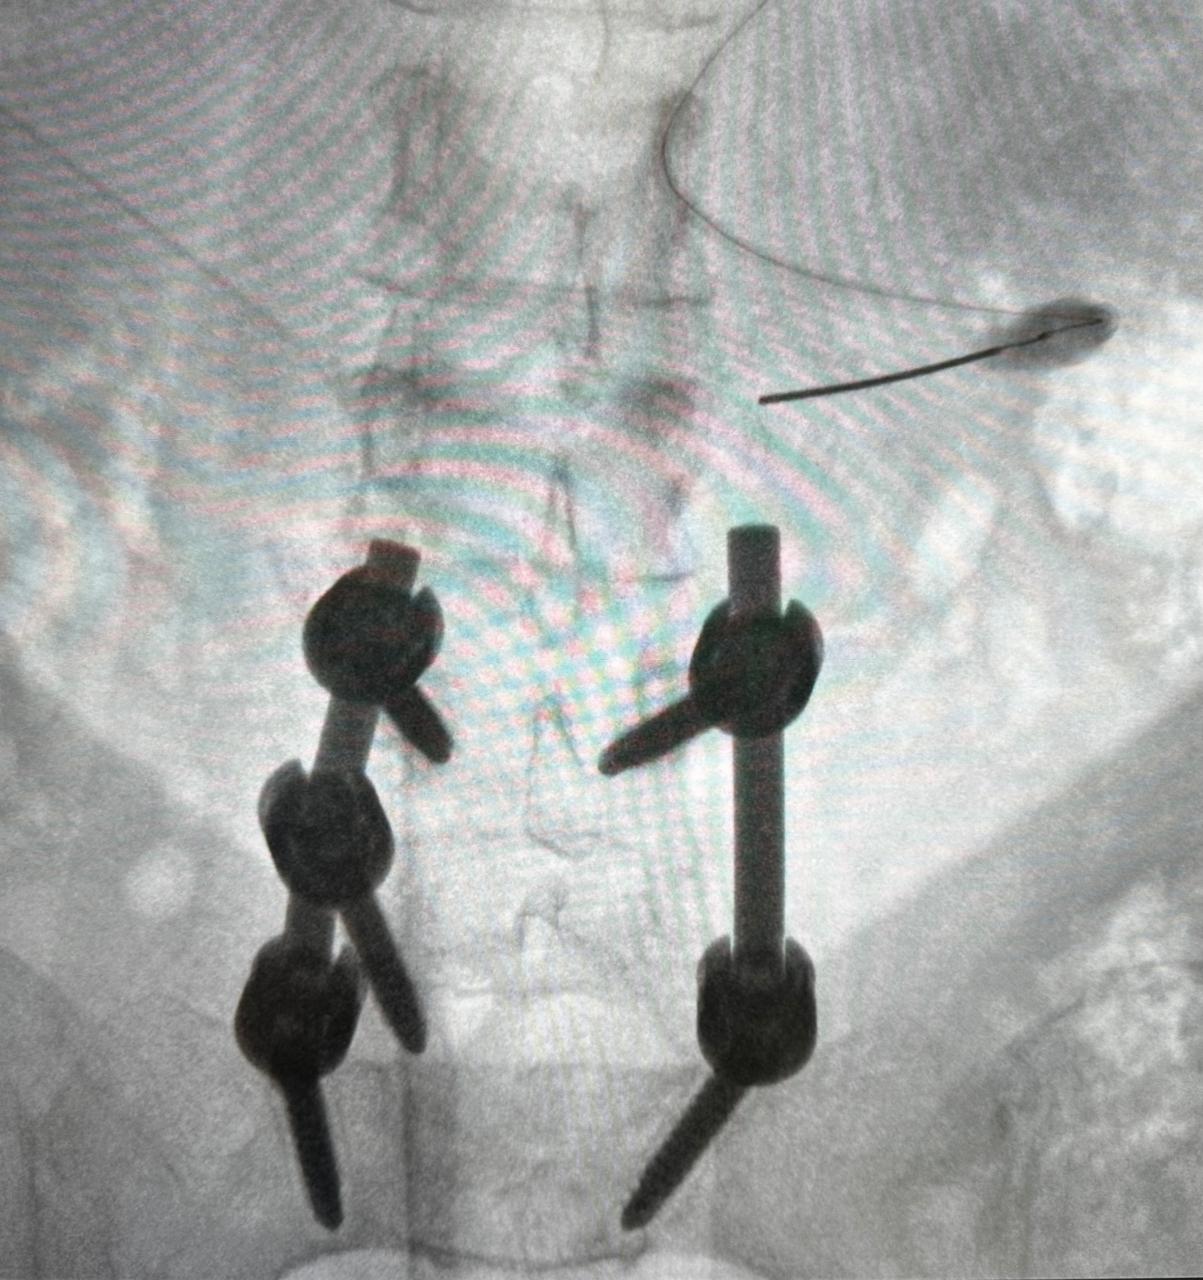

Tratamiento con diferentes técnicas en síndrome de espalda fallida ( post operatorio en columna )